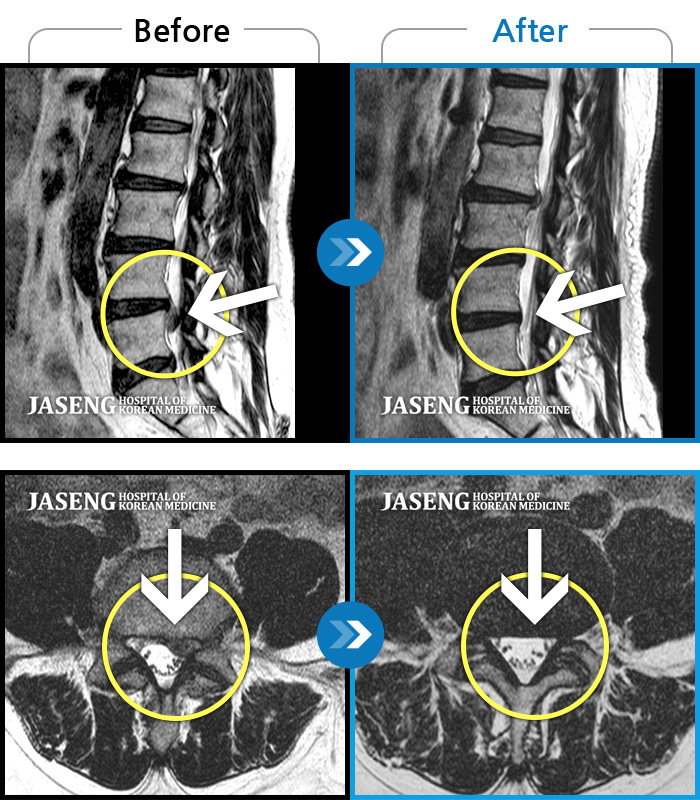

ȯںп Ǹ ǿ ԿǾ, ο ġ ۿ Ƿ ġḦ Ͻñ ٶϴ.